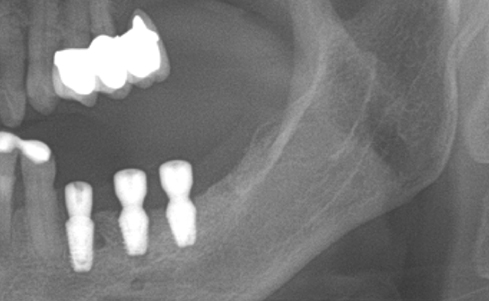

Simultaenous bone grafting for implants

Implants/Bone Grafting

Partial edentulous clinical cases